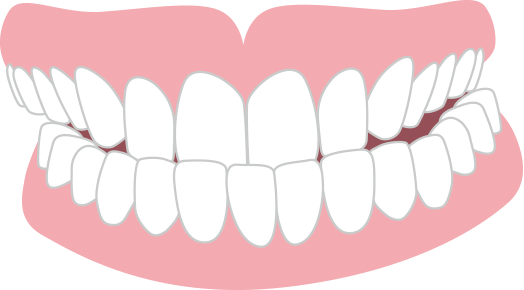

ガタガタ 叢生

あごと歯、それぞれの大きさのバランスが悪く、歯列にきれいにならびきらずに歯が重なったりねじれたりしている状態。

見た目に問題がある他、歯磨きがしづらく、虫歯や歯周病になりやすいです。